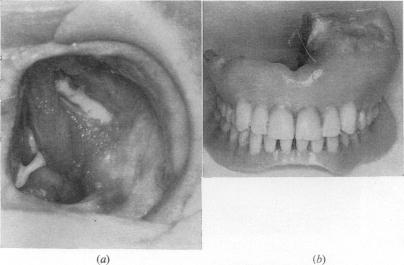

Prosthetics in otolaryngology.